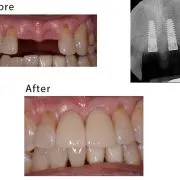

case-studies Case #3 This patient lost his teeth because of periodontal disease. They were restored with implant-supported crowns.February 26, 2024/by Rich https://sunnyvaledentalspecialty.com/wp-content/uploads/2018/08/blog2.jpg 512 614 Rich https://sunnyvaledentalspecialty.com/wp-content/uploads/2017/03/logo.png Rich2024-02-26 12:31:502024-05-02 11:09:46Case #3